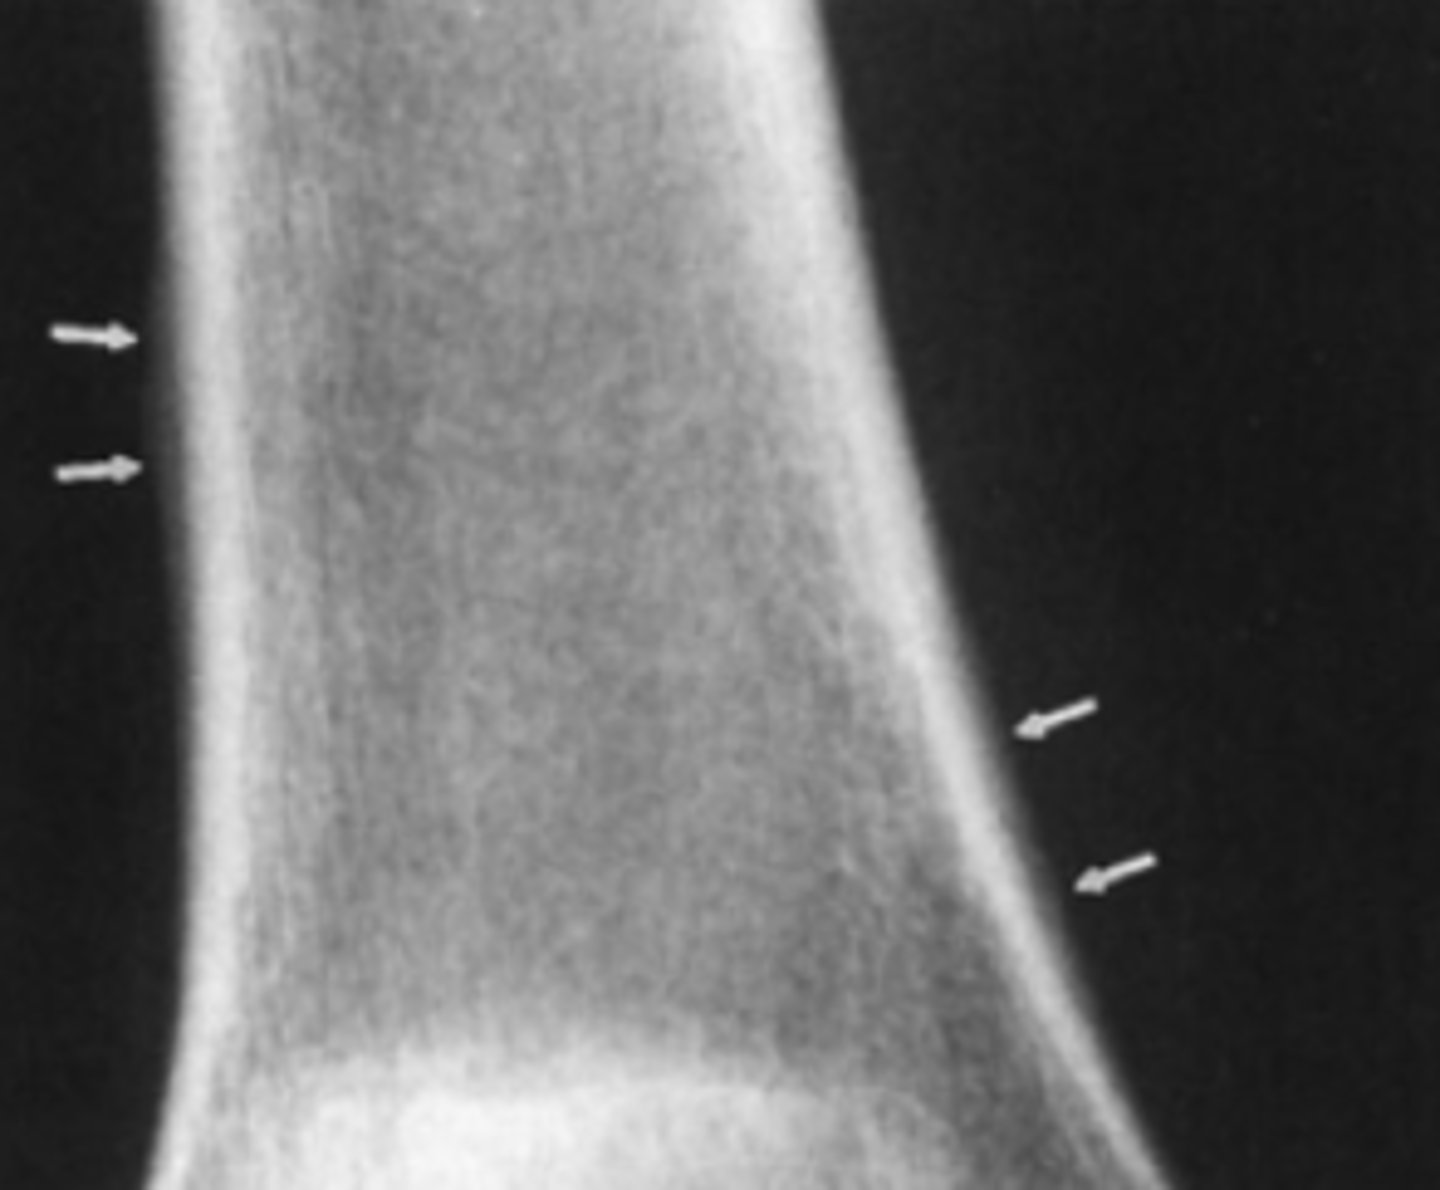

A 40-year-old man complains of knee pain and swelling of 3 weeks' duration. He has no other known disease. You order conventional radiographs of the knee.

For Case 6-11 (Figure 6-29), what is the next study

you should order?

A. Bone scan

B. MRI of the knee

C. Hand films

D. Chest radiograph

Answer

D.

A thin rim of calcium added to the bony contour of both sides of the right femoral metaphysis due to periosteal elevation. Similar findings are seen on the left femur and both tibiae

Periosteal elevation as seen in 6-11

Nonspecific finding that occurs with local disorders such as fracture, bone tumors, osteomyelitis, and bone infarction.

Hypertrophic osteoarthropathy

Characterized by chronic proliferative periostitis of long bones , clubing of fingers and synovitis, Its asso with Squamou cell carcnimoa and Adenocarcinoma of the lung.